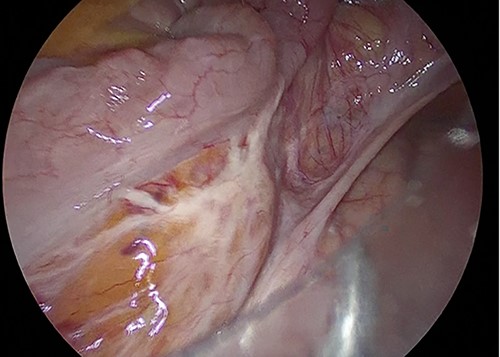

The sigmoid colon was elongated, and a scar was detected near the SD junction, which appeared to be a site of repeated torsion (Fig. 4). Dilation of the sigmoid colon revealed no inflammation on the serosal surface. The laparoscopic procedure was completed after confirming that the sigmoid colon was sufficiently elevated to the left lower abdomen. A 4-cm cross incision was made at the opposite of McBurney’s point, and the sigmoid colon was raised outside the wound (Fig. 5). The intestine was considered to be sufficiently decompressed to allow anastomosis. The intestinal tract was separated, and anastomotic reconstruction was performed using functional end-to-end anastomosis. The operation duration was 89 min, and the bleeding amount was 5 ml.

Surgical findings. Sigmoid colon was elongated and there was scar near the SD junction.